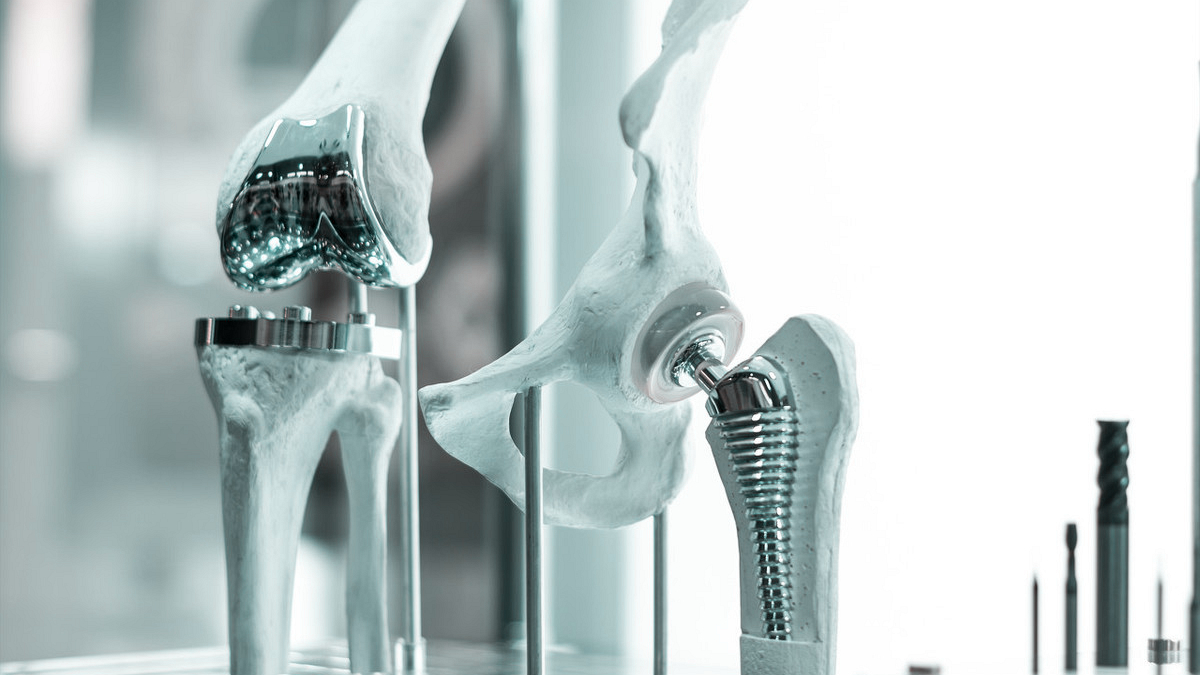

我们先了解一下什么是关节置换手术。

关节置换手术并不是人们所认为的将关节全部除掉,换上一个假的关节,它是将关节切开,然后去除病变的关节软骨及其下方部分骨质或者滑膜组织,将关节囊松懈,最后将预制好的关节假体放在骨表面或者内部,然后缝合关节,手术完毕。这种关节置换手术,只是切除了病变的部分,保护了关节的正常部分,达到了治疗的目的,更重要的是,关节置换手术成功的话可以有效的提高患者的生活质量。